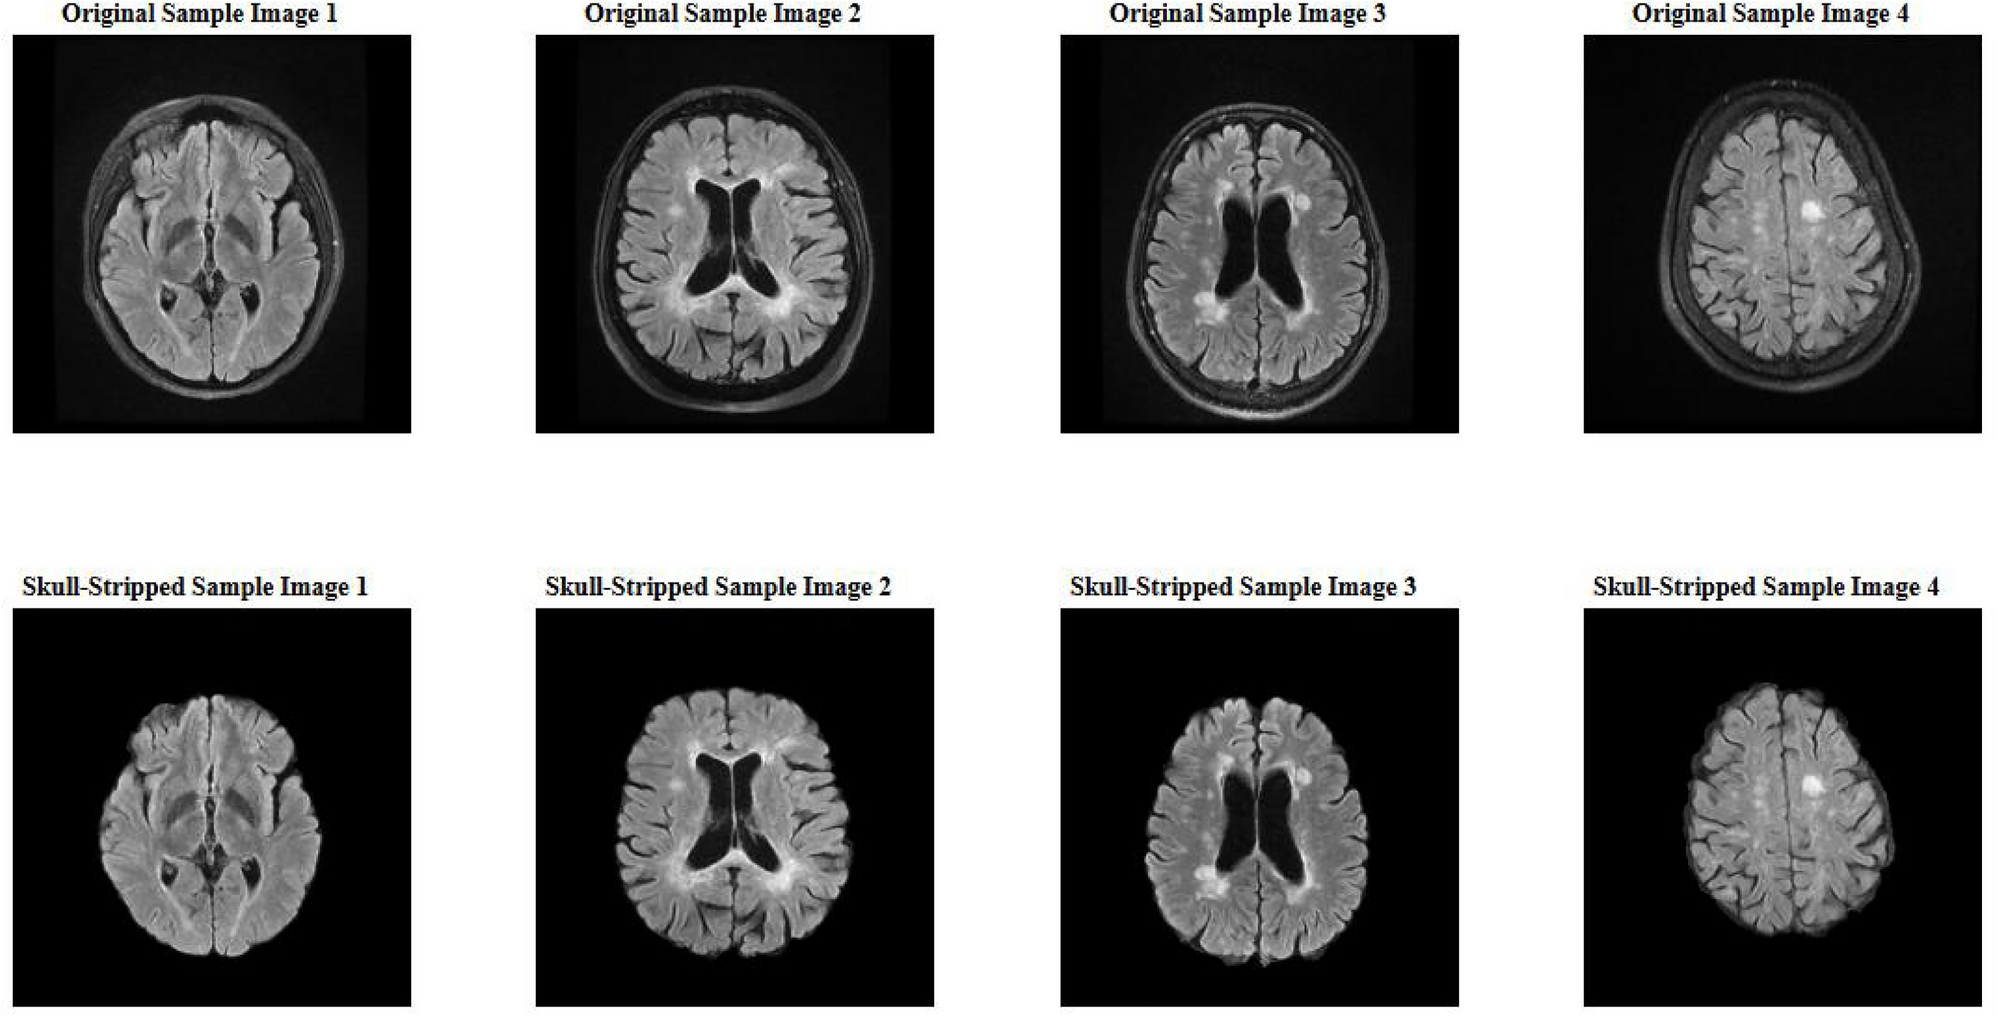

Fig. 1

Example of a skull-stripped FLAIR MRI image.